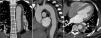

Ao oitavo dia de internamento foi repetida angioTC que mostrou um ligeiro aumento da espessura do hematoma (agora com cerca de 15mm), embora sem aumento da sua extensão longitudinal, e uma das ulcerações da parede da aorta apresentava um aspeto mais profundo e irregular (figura 2). O caso foi novamente discutido com a cirurgia cardiotorácica, tendo sido recusada intervenção cirúrgica, pelo que se manteve uma estratégia de vigilância e tratamento médico. O doente permaneceu clinicamente estável durante o internamento, tendo tido alta ao 19.° dia, medicado com quatro classes de anti‐hipertensores, incluindo bloqueador‐beta, orientado para a consulta externa de cardiologia e com controlo imagiológico agendado.

AngioTC de controlo ao oitavo dia mostrando um ligeiro aumento da espessura do hematoma (agora com 15mm e com um envolvimento em crescente da parede da aorta) (C), mantendo a sua extensão desde a subclávia esquerda até à emergência das artérias renais (A); uma das ulcerações da parede da aorta visualizadas na primeira angioTC apresentando um aspeto mais profundo e irregular (seta) (B).